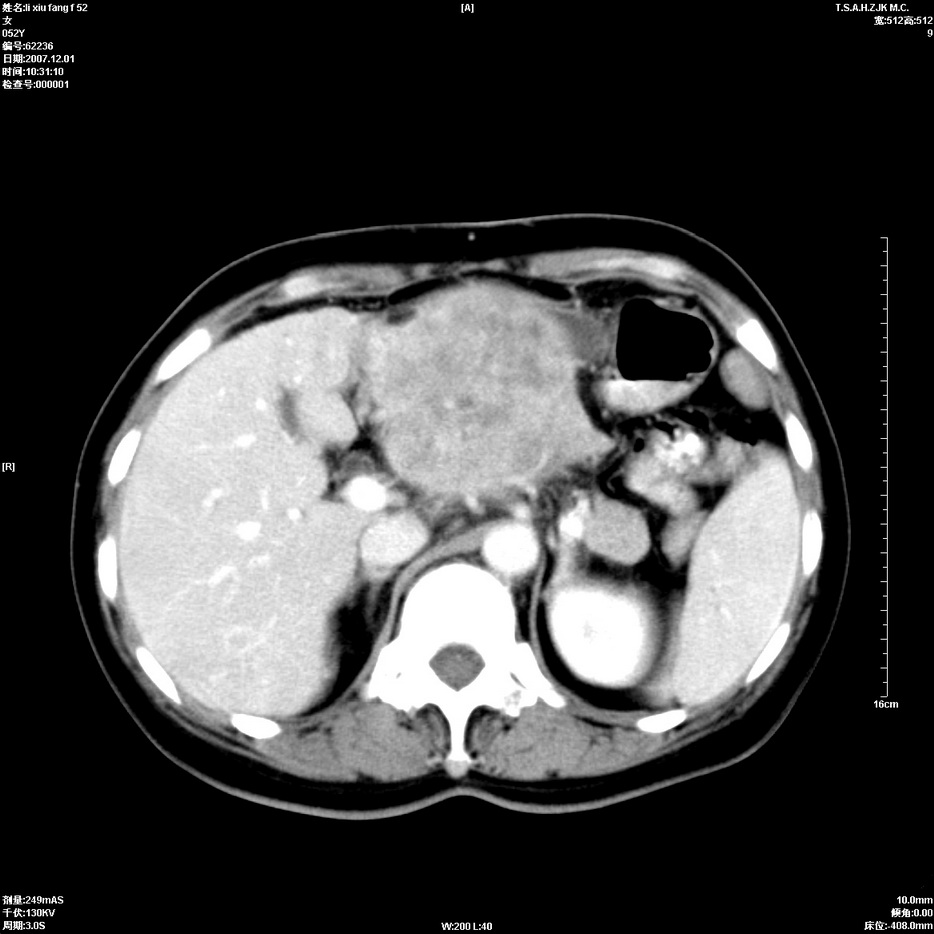

标题: CT12858:女,52岁,胎甲球蛋白861肝左叶占位,肝癌。下腔静 [打印本页]

标题: CT12858:女,52岁,胎甲球蛋白861肝左叶占位,肝癌。下腔静

肝左叶巨大低密度灶肿块,增强符合快进快出表现,有动静脉交通支;静脉期,下腔静脉内有充盈缺损,afp明显升高,支持肝癌并下腔静脉癌栓形成。

支持楼主   门静脉主干及左支癌栓形成

以下是引用拾荒者在2008-4-15 22:57:00的发言:[br]肝左叶巨大低密度灶肿块,增强符合快进快出表现,有动静脉交通支;静脉期,下腔静脉内有充盈缺损,afp明显升高,支持肝癌并下腔静脉癌栓形成。